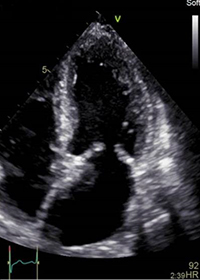

従来の超音波装置による診断画像 |

Vivid E95/90による高画質診断画像 |

従来のハードウェアによる超音波送受信を全てソフトウェアで行うことにより,より多くの送受信情報(ローカルビッグデータ)を高速演算処理ユニットで同時並列多重プロセスから画像化することに成功。高画質と高フレームレート(リアルタイム性)の両立を実現した。

全深度,全視野においてピクセルレベルで焦点の合った,鮮明度の高い画像の提供を可能とする「ダイナミックピクセルフォーカス機能」と「Adaptive Contrast Enhance 機能」を搭載。